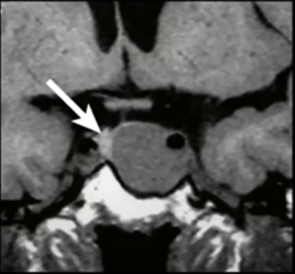

IRM des pathologies hypophysaires

TSHIBANDA L. – ULG